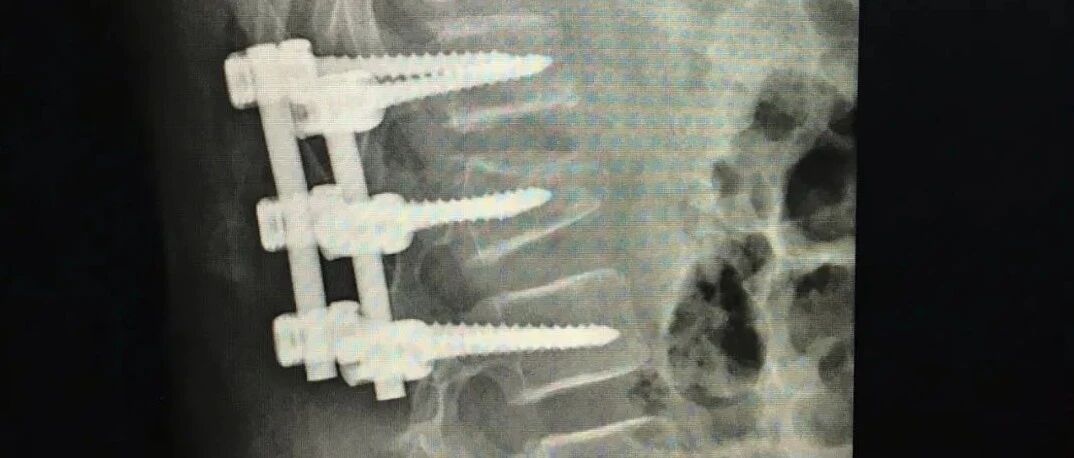

浙江11岁女孩玩蹦床摔成爆裂性骨折,腰椎打了3根钉子!类似事故已发生多起